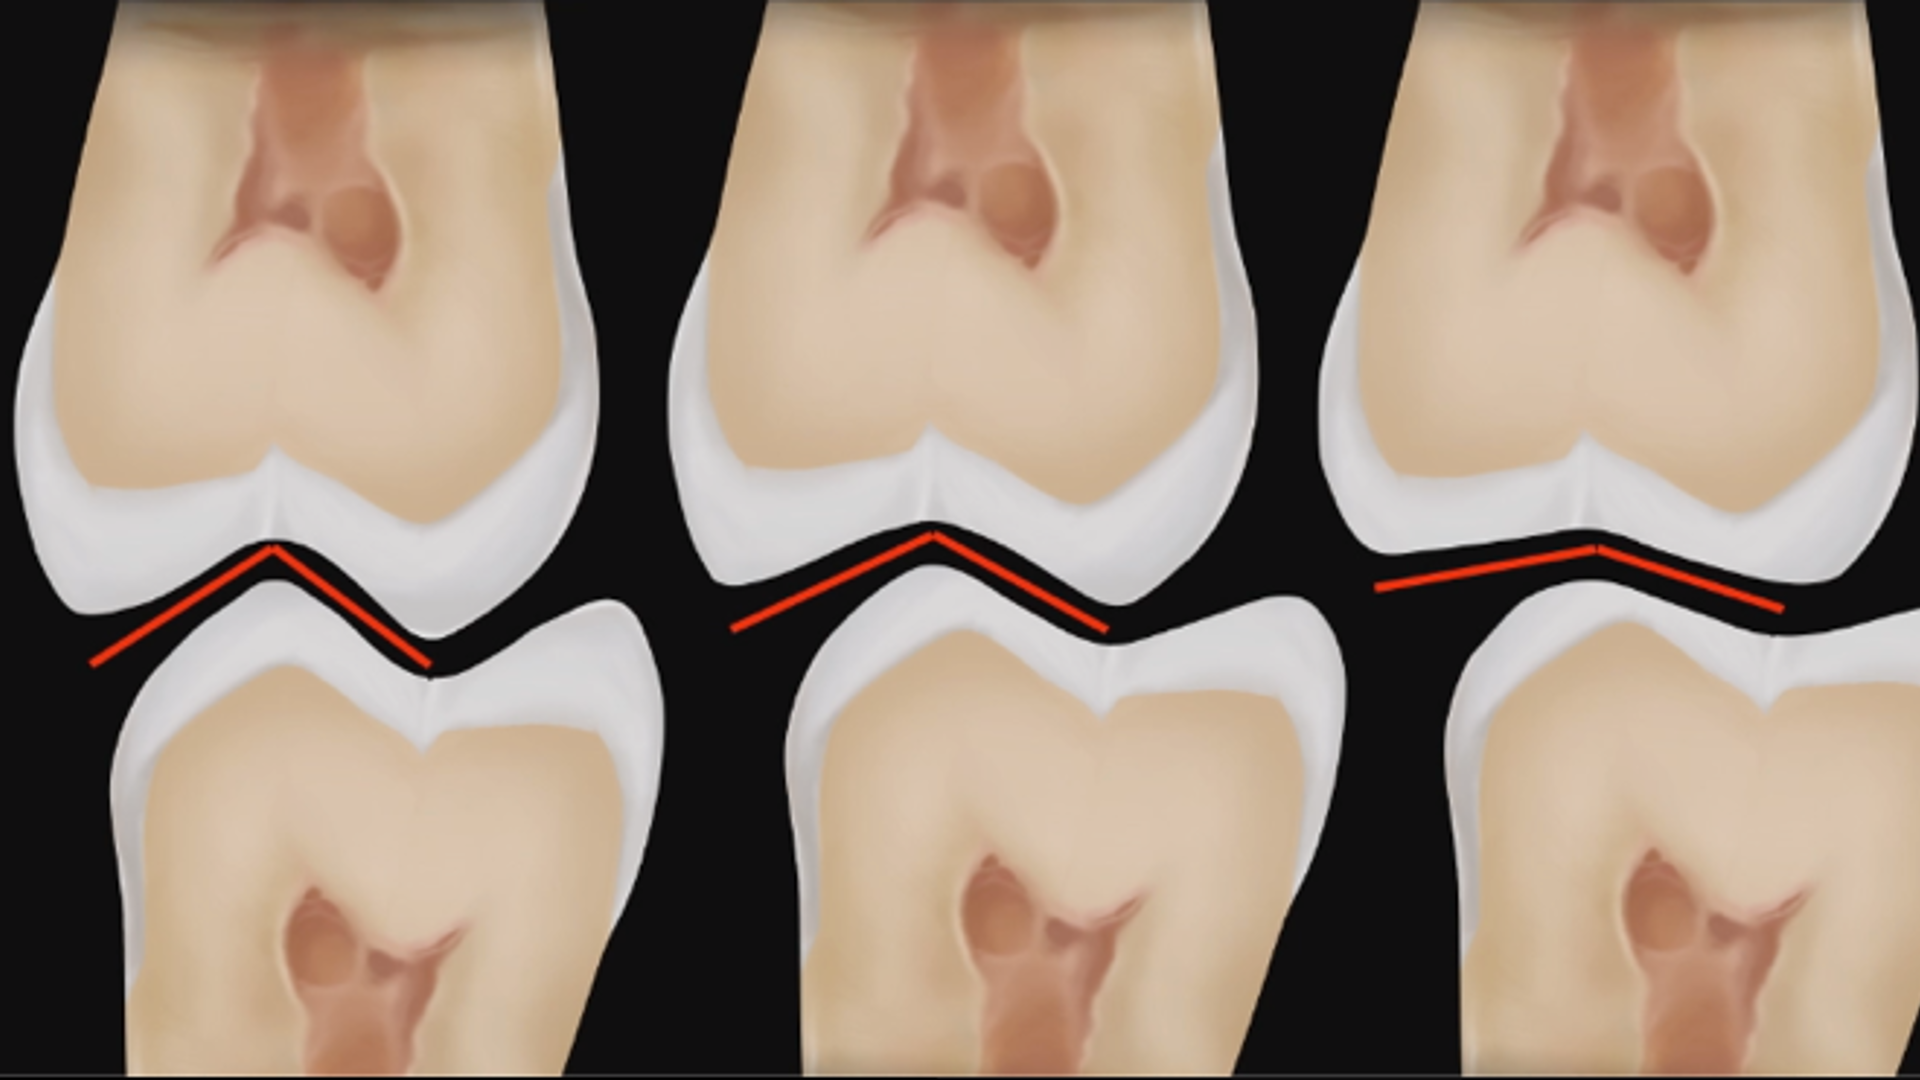

Occlusion vertical size according to MIPP concept